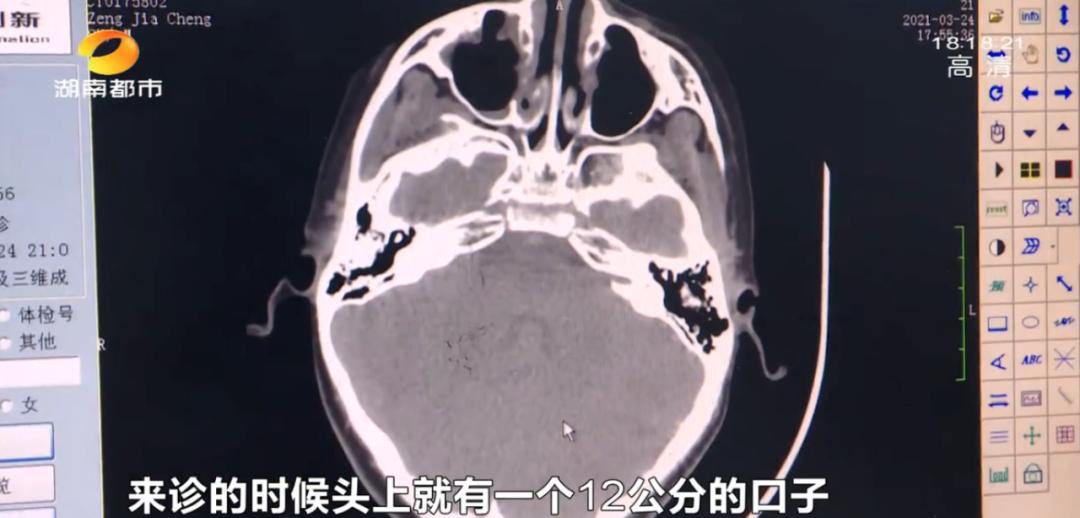

救護(hù)車抵達(dá)醫(yī)院后,醫(yī)護(hù)人員立即為孩子縫合傷口,并安排進(jìn)行頭部CT檢查,所幸檢查及時(shí),孩子確診為蛛網(wǎng)膜下腔出血,是典型因腦外傷導(dǎo)致顱內(nèi)出血的案例。目前孩子已無大礙,正在院進(jìn)一步檢查治療。

經(jīng)CT檢查,醫(yī)生發(fā)現(xiàn)孩子因外傷導(dǎo)致了腦挫裂傷及蛛網(wǎng)膜下腔出血,所幸檢查及時(shí)且出血量不大,無需手術(shù)治療,對(duì)孩子的傷口進(jìn)行清創(chuàng)縫合后,目前情況暫無大礙。